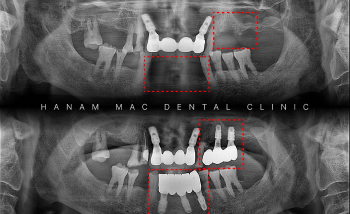

[임플란트 치료 기록] 하악 전치부 임플란트 및 상악동 거상술 동반 어금니 식립 69세 환자분께서 "아래 앞니 임플란트하고 싶어요"라는 C.C...